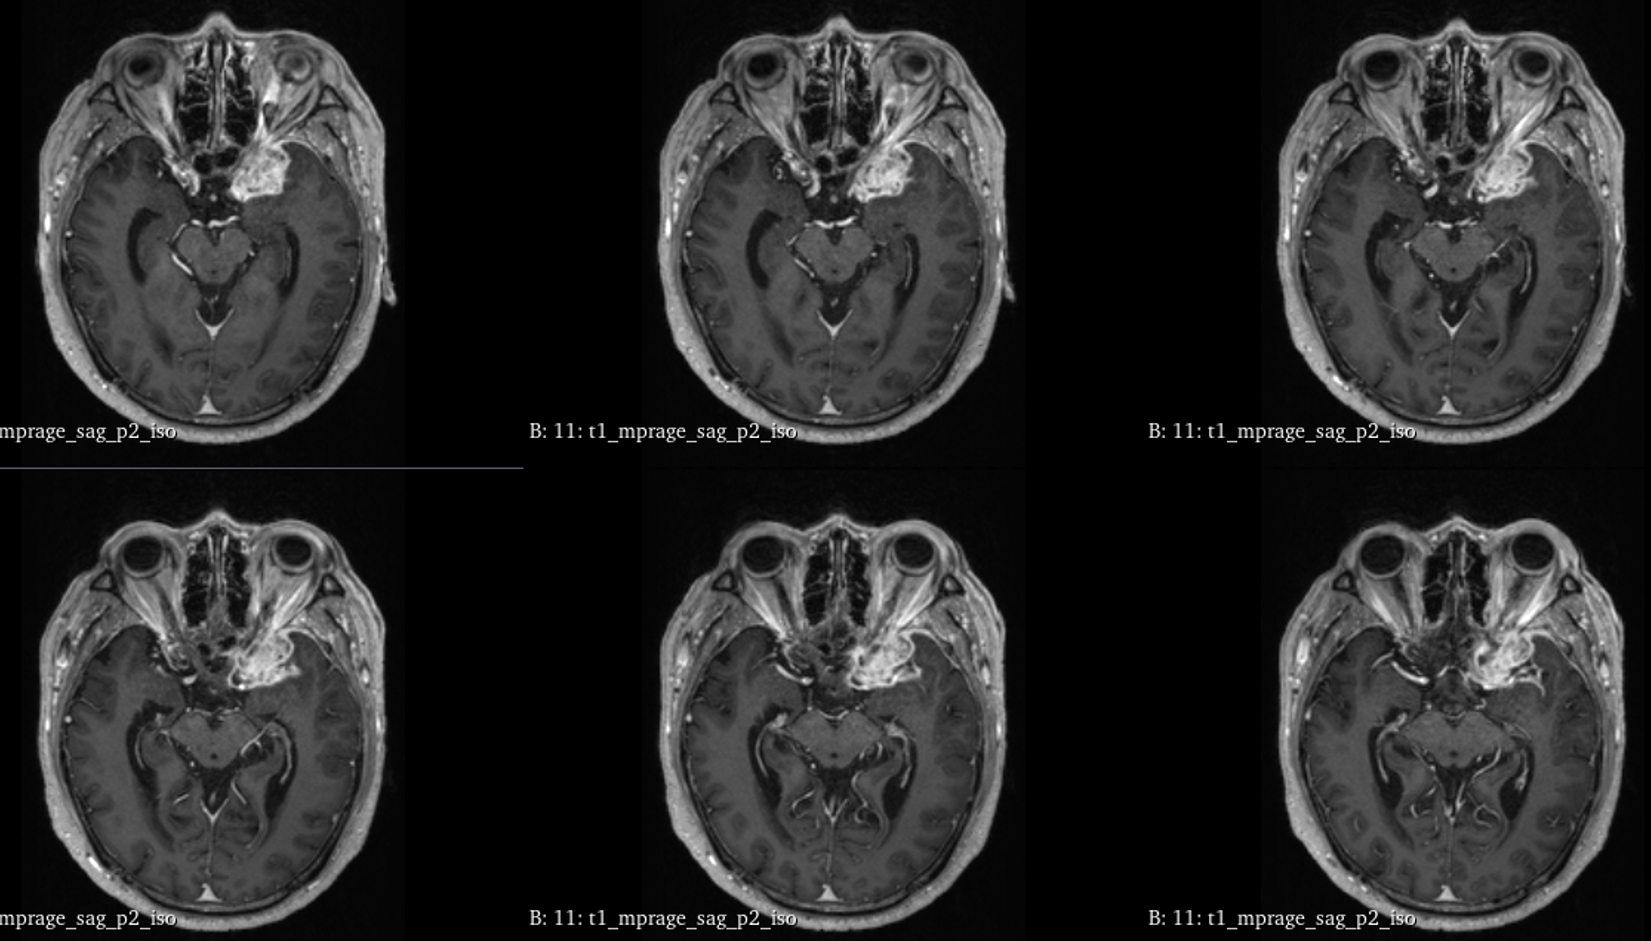

该患者入院后完善常规颅脑影像学检查,左侧颞叶病变,疾病性质不详,转移瘤、胶质瘤、炎症类疾病均不能排除,遂行PET-CT检查,提示左侧颞叶高代谢,淋巴瘤不能排除。组织MDT会诊建议可先行腰椎穿刺查脑脊液脱落细胞学、感染指标,若仍不能确诊,可进一步行开颅病灶切除,术中快速冰冻,根据冰冻结果决定手术手术策略。患者脑脊液脱落细胞学结果:较多淋巴细胞,少许单核细胞及个别中性粒细胞,未见异形细胞,脑脊液常规、生化、脑脊液培养未见细菌生长,诊断仍不能明确,且患者病情进展迅速,患者神志呈昏睡状态,颅脑MRI提示病变较前明显增大(影像学检查间隔两周),且水肿明显加重,遂行开颅病变切除术。术中见部分病变累及蝶骨嵴硬膜,病变质地硬韧,内有多个囊腔,囊内容物为黄色粘稠样脓性物质,留取囊液及实性部分送快速冰冻,在等待冰冻过程中,进一步探查见肿瘤侵犯左侧颞叶,该部位肿瘤质地相对软,无包膜,与周围脑组织无边界,血运不丰富,内有多个囊腔,且肿瘤侵犯侧裂池、颈动脉池,左侧视神经、颈内动脉、大脑中动脉均被病变包绕,且该处肿瘤质地偏硬韧。术中快速冰冻提示组织大片变性坏死,伴胶质增生及淋巴增生。结合病变质地及冰冻结果,考虑为非肿瘤性疾病,可能为炎性病变伴肉芽肿形成可能性大,且肿瘤质地硬韧,累及范围广泛,难以全切,遂行肿瘤大部分切除后结束手术。术后病理结果明确后予以伏立康唑、醋酸卡泊芬净抗真菌治疗。在治疗过程中患者先后出现脑出血、脑梗塞,最终因治疗周期长,花费高、效果不确定等因素,家属放弃治疗,于术后1月去世。

颅内曲霉菌病(intracranial aspergillosis,ICA),又称中枢神经系统曲霉菌病,是一种由曲霉菌侵袭感染脑实质、脑膜(硬脑膜为主)、脑血管及海绵窦等颅底结构引起的侵袭性真菌病。ICA由Oppe首次报道于1897年,该病临床少见,但随着激素、免疫抑制剂及广谱抗生素的广泛应用,其发病率逐年上升。ICA的临床及影像学表现缺乏特异性,核心症状异质性大,诊断及鉴别诊断困难。ICA占颅内真菌感染的5%-10%,占侵袭性曲霉菌感染的14%-42%,ICA更易累及男性,男女比例为2.25∶1。曲霉菌在自然界中广泛存在,是一种机会致病菌。其分生孢子可经呼吸道进入人体,定植于肺部、鼻窦等空腔内。当机体免疫力降低时,曲霉菌在组织、器官或血液中生长、繁殖,导致炎性反应及组织损伤,可经两种途径即局部浸润及血行播散侵入颅内导致ICA。据报道,18.0%-66.7%的患者由鼻窦、中耳及乳突中的曲霉菌感染浸润引起(窦源性ICA),该患者合并慢性鼻窦炎,考虑为窦源性。ICA可累及脑血管、脑实质、脑膜(硬脑膜为主)及颅底结构,导致坏死、化脓及慢性肉芽肿。曲霉菌侵及脑血管后,既可因菌丝填充或炎性反应导致脑梗死,又可因曲霉菌性动脉瘤破裂导致脑出血或蛛网膜下腔出血。该病多呈急性或亚急性起病,进行性加重,临床表现多样且缺乏特异性。

GM实验,GM是曲霉菌细胞壁的主要成分,是疾病早期释放至体液中的抗原之一。据报道,脑脊液GM试验诊断ICA的敏感度及特异度分别为88.2%及96.3%,且阳性预测值及阴性预测值均超过90%,脑脊液GM水平与曲霉菌感染严重程度相关,监测该指标可评价治疗效果及预后。影像学检查具有多样性,多为反复慢性炎症、肉芽肿样改变,部分易累及颅底。

目前确诊ICA仍依赖于病灶切除或活检,获得组织病理学、直接镜检或培养证据。《颅内曲霉菌病诊治中国专家共识》推荐:当临床症状怀疑ICA时,应尽早行脑脊液检查(常规、生化、培养、G试验、GM试验及mNGS)及颅脑MRI平扫+增强检查。怀疑窦源性ICA时,还应加做颅底CT检查。当临床症状符合ICA,但上述检查结果为阴性时,可重复送检。条件允许时,及时行标本镜检与培养获得确切证据。尤其是对于长期应用激素、免疫功能缺陷高危患者。